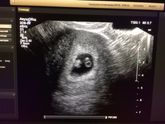

А вот и он, долгожданный и неожиданный. Теперь я ещё больше чувствую себя беременной - это о плюсах :)

Ну вот, сходила. По УЗИ тянем недельки на 2,5 — 3, в принципе так и получается, у меня поздняя О. Всё на положенном месте, видно хорошо)